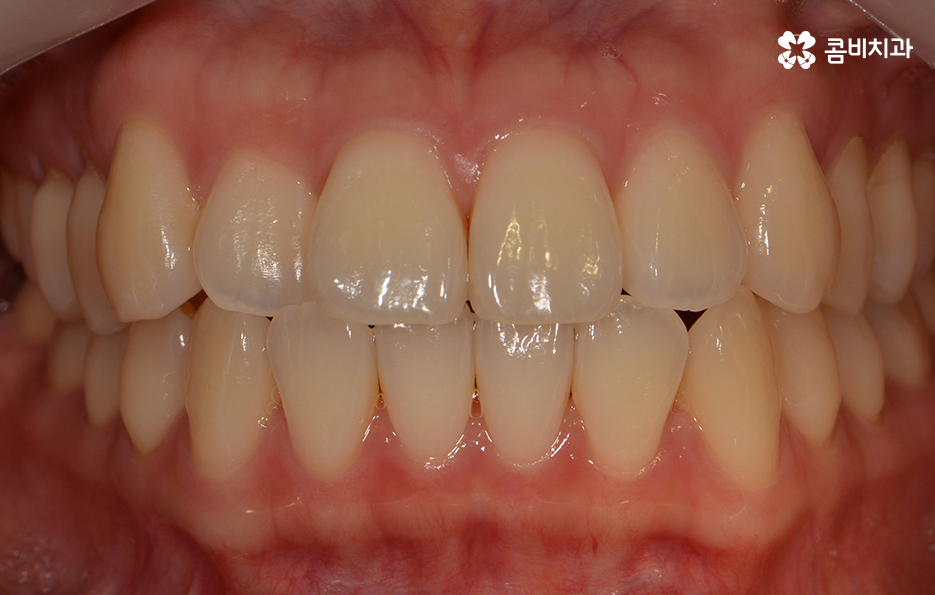

돌출된 앞니로 인해서 교정을 원하신 상황이며 치료 전 치아 상태

치열의 상태가 정면으로 바라봤을 때 비교적 가지런한 편이지만

측면으로 볼 때 유독 앞으로 돌출된 경우라면

입모양과 얼굴형에도 영향을 주기 때문에

앞니치아교정을 알아보시는 분들 중에서

이러한 고민으로 인해 치료를 원하시는 경우가 많습니다.